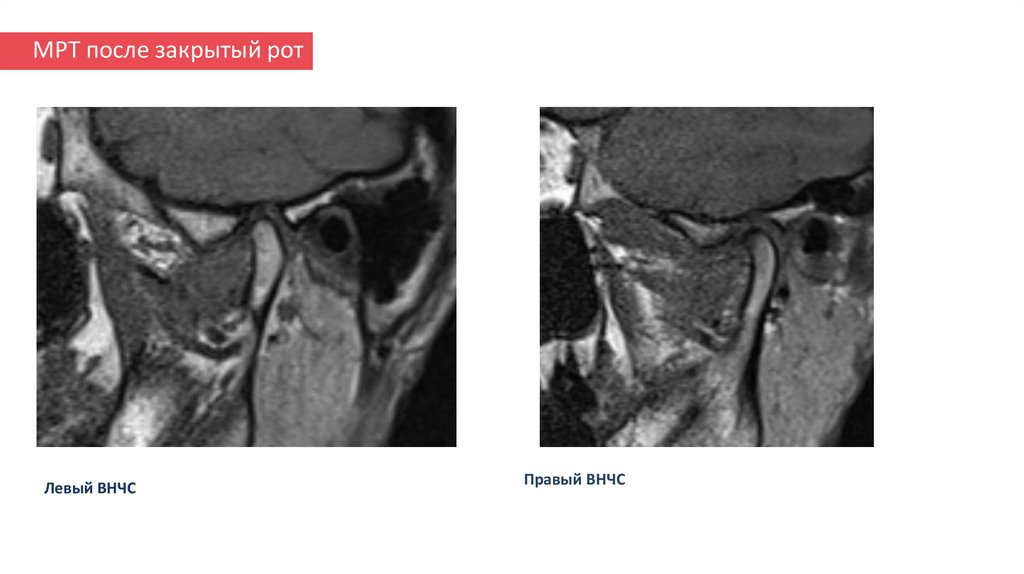

19. МРТ после закрытый рот

Левый ВНЧС

Правый ВНЧС